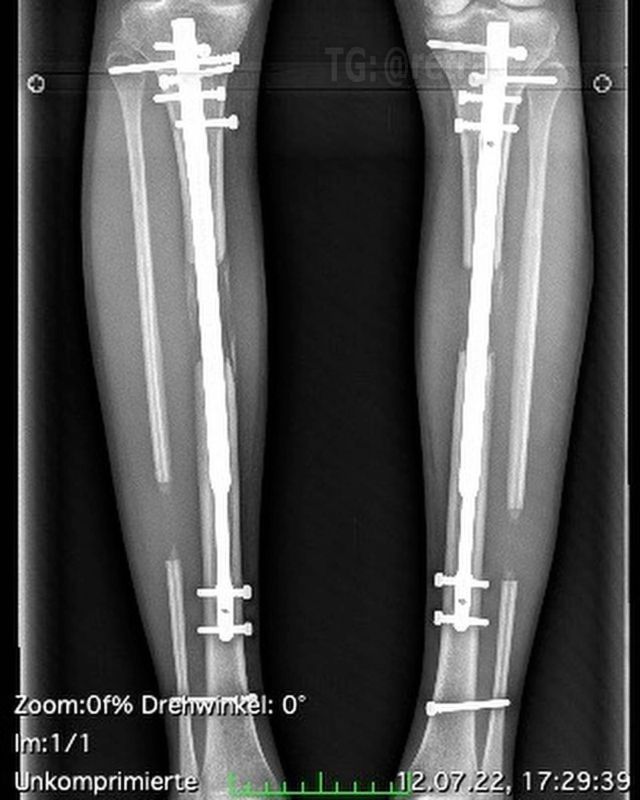

Процесс удлинения ног требует болезненной процедуры, при которой врач ломает кости в каждой ноге пациента и вставляет регулируемые телескопические стержни. В течение следующих трёх месяцев ноги постепенно удлиняются на один миллиметр в день, что в конечном итоге делает человека на несколько сантиметров выше. Операция также влечёт за собой длительный процесс восстановления с «непрекращающейся» болью из-за растяжения нервов, мышц и тканей ног.